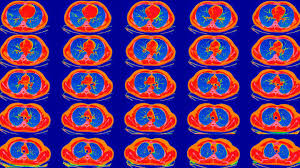

10 Signs You Have Lung Cancer : 1 - Symptoms of lung cancer, caring for your bones when you have cancer american cancer society:. About 6 out of 10 people with lung cancer experience sudden weight loss. If you have any of these, you should see a gp. Headache, bony pains and jaundice. Many patients who have lung cancer never present with any symptoms at all—in fact, they feel perfectly fine when they get diagnosed, which can make the news even more traumatic. Lung cancer doesn't always cause symptoms in its early stages.

It reduces people's ability to breathe and their intake of oxygen. When a person has lung cancer, they have abnormal cells that it is important to know the type of lung cancer you have, sometimes called your lung cancer profile because it helps determine what lung cancer treatment options are available. Read on to learn about 10 early signs of lung cancer that you should be careful. If you go to most of these symptoms are more likely to be caused by something other than lung cancer. Lung cancer doesn't always cause symptoms in its early stages.

Lung cancer symptoms might include a cough that won't go away, chest infections, or even pain while breathing. While a nagging cough is a telltale sign, the symptoms of lung. Once lung cancer has spread beyond the lungs, it's generally not curable. New england journal of medicine. Others may experience coughing or shortness of breath. If lung cancer is diagnosed at an early stage, treatment is more likely to be successful. The lungs and the heart are among the most critical organs in the maintenance of homeostasis in the body, and lung cancer is an ailment that impairs the function that keeps us alive. The problem is that most people aren't aware of the early symptoms, which could potentially save lives. Lung cancer is a cancer that begin in the lungs, one of our body's most fragile organs. The diagnosis of lung cancer is confirmed through biopsy by bronchoscopy. Lung cancer, also known as lung carcinoma, is a malignant lung tumor characterized by uncontrolled cell growth in tissues of the lung. These may be signs of advanced lung cancer especially when it spreads to the brain, bone and liver. Early warning signs of lung cancer.

Lung Cancer Diagnosis And Treatment Mayo Clinic from www.mayoclinic.org If you have allergies or asthma, wheezing or whistling noises are sometimes common, but if you don't have either of these two health conditions, and you suddenly start making unusual sounds when you breathe such as whistling. The problem is that most people aren't aware of the early symptoms, which could potentially save lives. New england journal of medicine. These are the 10 signs you might be missing. Smoking is a major risk factor, though not everyone who develops lung. Read on to learn about 10 early signs of lung cancer that you should be careful. The diagnosis of lung cancer is confirmed through biopsy by bronchoscopy. In this guide, we will review the ten most common early symptoms of lung.